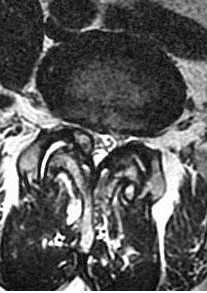

Остеоартроз приводит к уменьшению бокового кармана (в норме 5 мм на поясничном уровне). Синовиальная суставная жидкость может выходить через щели в капсуле сустава и осумковываться, образуя кисту. Типичное место расположения синовиальных кист - уровень диска L4-5. На КТ киста гипо- или гиперденсна, в ее стенке могут быть кальцинаты. При МРТ позвоночника синовиальная киста гипо- или слегка гиперинтенсивна на Т2-зависимых МРТ изображениях.

МРТ поясничного отдела позвоночника. Синовиальная киста справа. Аксиальная Т2-взвешенная МРТ.